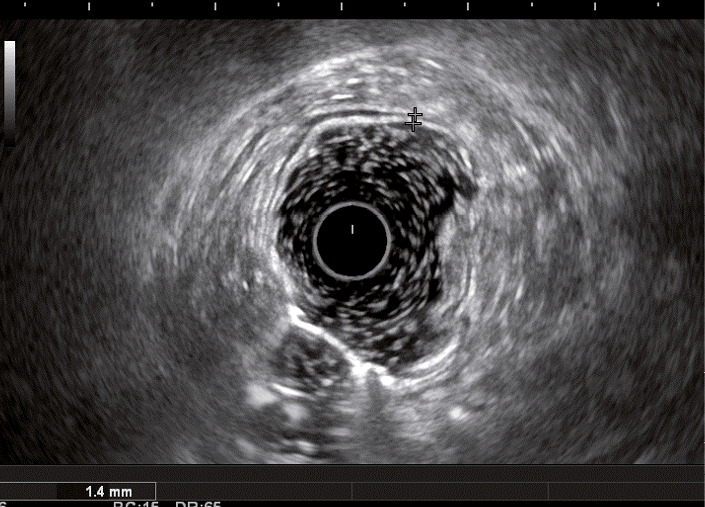

При ВЗК в стадии обострения стенка кишки утолщается, при этом в зависимости от нозологии увеличение размера кишки происходит за счет разных слоев кишечной стенки (рис. 1–4).

Рис. 2. Эндосонографическая картина стенки толстой кишки в норме

Рис. 3. Эндосонографическая картина толстой кишки при язвенном колите; 1 – утолщение слизисто-подслизистого слоя; 2 – утолщение стенки толстой кишки

Толщина стенки толстой кишки при ЯК была в диапазоне от 2,7 до 5,5 мм (3,96 ± 0,13), при БК – от 3 до 11 мм (5,66 ± 0,36), в контрольной группе данный показатель не превышал 3,1 мм, а минимальная толщина была 1,6 мм (2,62 ± 0,11). Анализ толщины стенки в разных группах выявил статистически значимую разницу величины показателей между больными с ВЗК и группой контроля (р = 0,002), между ЯК и БК (р = 0,002). При этом при сравнении БК и группы контроля коэффициент достоверности оказался выше, чем при ЯК (р < 0,001 и р = 0,002 соответственно) (см. рис. 1).

Кишечная стенка статистически значимо чаще утолщалась за счет слизисто-подслизистого слоя при ЯК, чем при БК: в 82 и 7,14% соответственно; диагностическая чувствительность данного признака была 82%, а специфичность – 93% (табл. 1). При БК изменение стенки толстой кишки за счет трансмурального утолщения выявлялось статистически значимо чаще (68%), чем при ЯК (9%) (чувствительность 68%, специфичность 91%). Статистически значимых различий в частоте изменений мышечного слоя кишки отмечено не было. Только при БК в 68% случаев отсутствовала дифференцировка слоев кишечной стенки в фазе обострения (чувствительность и специфичность признака составили 68 и 100% соответственно) (см. рис. 4). При ЯК на фоне «смазанности» слизисто-подслизистого слоя у всех больных можно было визуализировать мышечный и серозный слои (см. табл. 1, рис. 3).